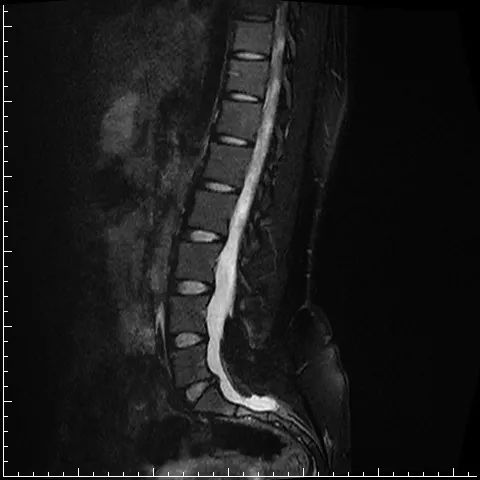

图:术前MRI从小王的口中我们得知,她曾先后做过跟腱延长、肌腱转位以及胫腓骨延长等手术,由于时日久远,小王也无法准确地回忆起手术具体的内容。然而尽管做了这么多手术,她走路时依旧又慢又跛,脚底也因为长期的负重不平衡而饱受疼痛。她的左脚是扁平足,右脚是高弓马蹄内翻足,这两种截然不同的足畸形却发生在同一个人身上。结合患者腰痛的主诉,我们对其进行了腰椎MRI检查,显示腰4-骶2水平的椎管内有一个低信号的团块,这样一来,原因便清楚了。

“脊髓拴系综合征?”听着这个名词,小王一脸的茫然,这20多年来从未有人告诉过她,她先天性双足畸形的原因竟在腰上。脊髓拴系综合征,是脊柱裂患者在胚胎期同时出现脊髓发育异常、局部瘢痕粘连、终丝缩短,造成脊髓固定于病变部位、不能适应脊柱的增长而上升,使脊髓、马尾神经和终丝受到牵拉,可造成腰背部疼痛、双下肢和二便功能障碍。虽然病因明确了,但这一疾病却没有办法根治,那么如何提升患者的生活质量,改善患者的步态,就成了治疗的主要目标。